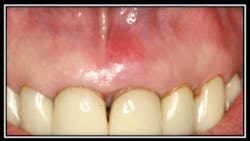

Case #1: Horizontal Root Fracture #9

By Robert Gottlieb, DDS, and Suzanne Newkirk, RDH

Root fractures that develop communication between the gingival sulcus and the fracture site have a poor prognosis because of bacterial contamination.

Due to the extent of the above fracture, treatment recommendations for this patient included extraction and immediate implant placement, which the patient proceeded with.